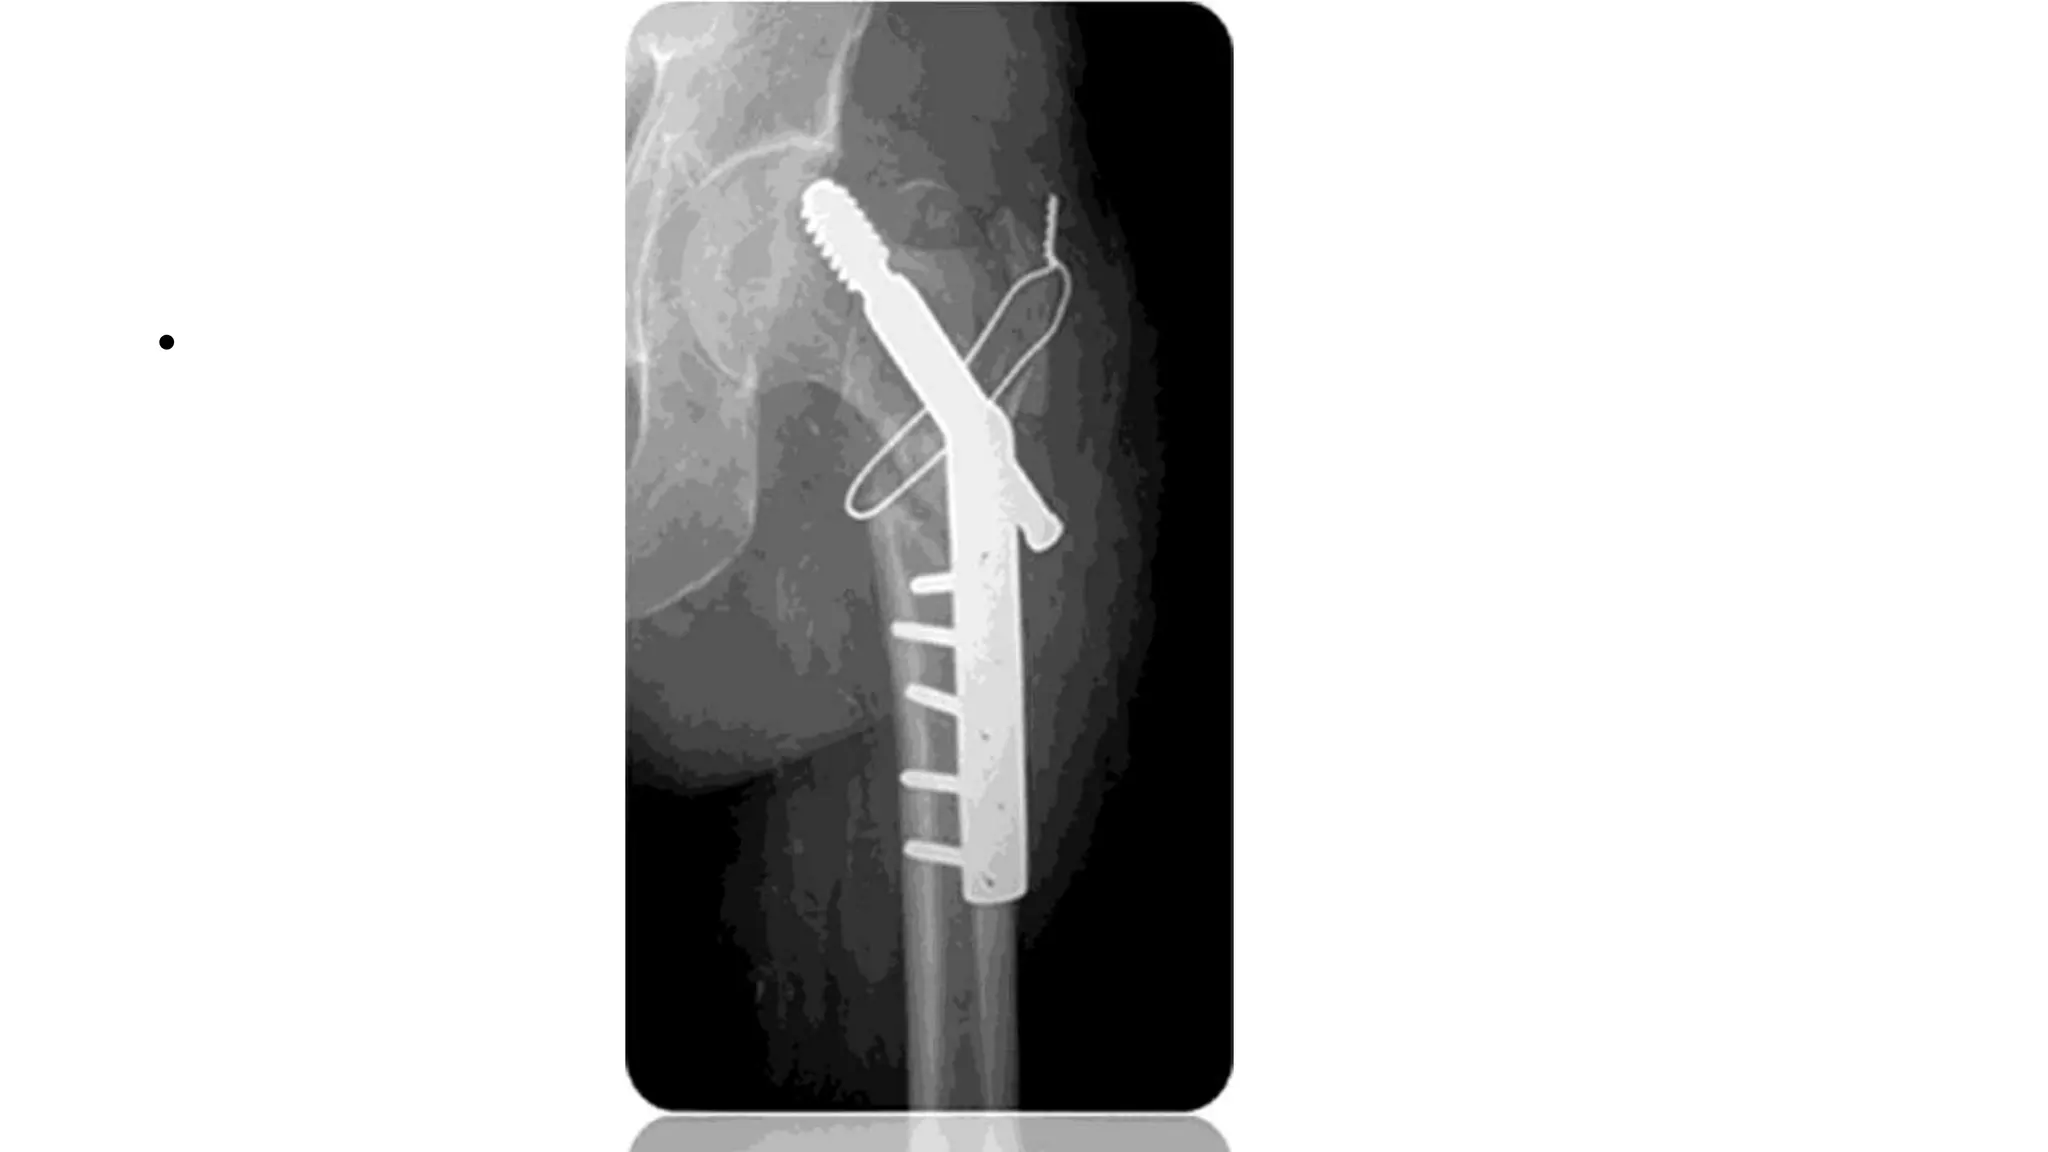

Keyed system

• Traction released

• Angled plate acts as an aid to

reduction

• Intraop prox displacement of

femoral shaft along the plate

before screw insertion

• Post op as lag screw collapses into

the barrel by impaction

• Compression screw-also

prevents postop hip screw barrel

disengagement

Complication

• 31.

• Traction released •Angled plate acts as an aid to reduction • Intraop prox displacement of femoral shaft along the plate before screw insertion • Post op as lag screw collapses into the barrel by impaction • Compression screw-also prevents postop hip screw barrel disengagement